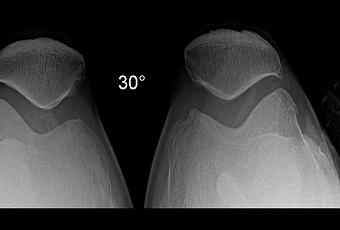

RADIOGRAFIA AP, LATERAL Y AXIALES DE RODILLAS

Se identifican las estructuras óseas de rodillas fémur distal, tibia, peroné proximal y rotula con adecuada mineralización, sin evidencia de fractura. Existe material por artroplastia nivel de tibia izquierda, así como área de atomización en parte distal de fémur izquierdo.

Rotulas tipo II de Wiberg.

Los espacios articulares patelofemorales, derecho con disminución leve de su amplitud de izquierdo con adecuada amplitud.

-Angulo Muñiz derecho de 6.7 ° e izquierdo de -12.7 °

-Ángulo patelofemoral, ambos con vértice medial.

Angulo intercondileo derecho 105.3° e izquierdo 106.5 °

Angulo de congruencia derecho – 11.2 ° e izquierdo de -7.1 °

EN EL PRESENTE ESTUDIO RADIOGRÁFICO, EXISTE DESPLAZAMIENTO LATERAL DE RÓTULA IZQUIERDA.

EXISTE MATERIAL Y CAMBIOS DE ARTROPLASTIA EN RODILLA IZQUIERDA.